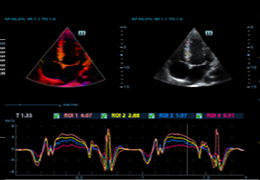

ANYTHINK 经导管主动脉瓣膜置换术分析系统